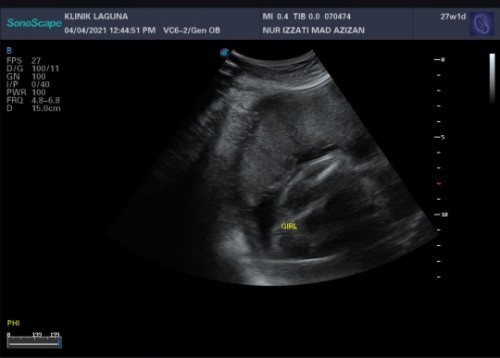

Girl atau boy

Hi mommies, boleh tahu kalau macamni memang confirm girl ke?

tu lapisan beger 😝 same mcm sy .. perot mcm boy .. tp bnyk kali dokter scan .. ckp girl sbb lapisan beger .. bkn bobird 😆

hehe.. sy baru first time scan.. tu confuse.. sbb time san pun dia malu2 nak tunjuk🤭